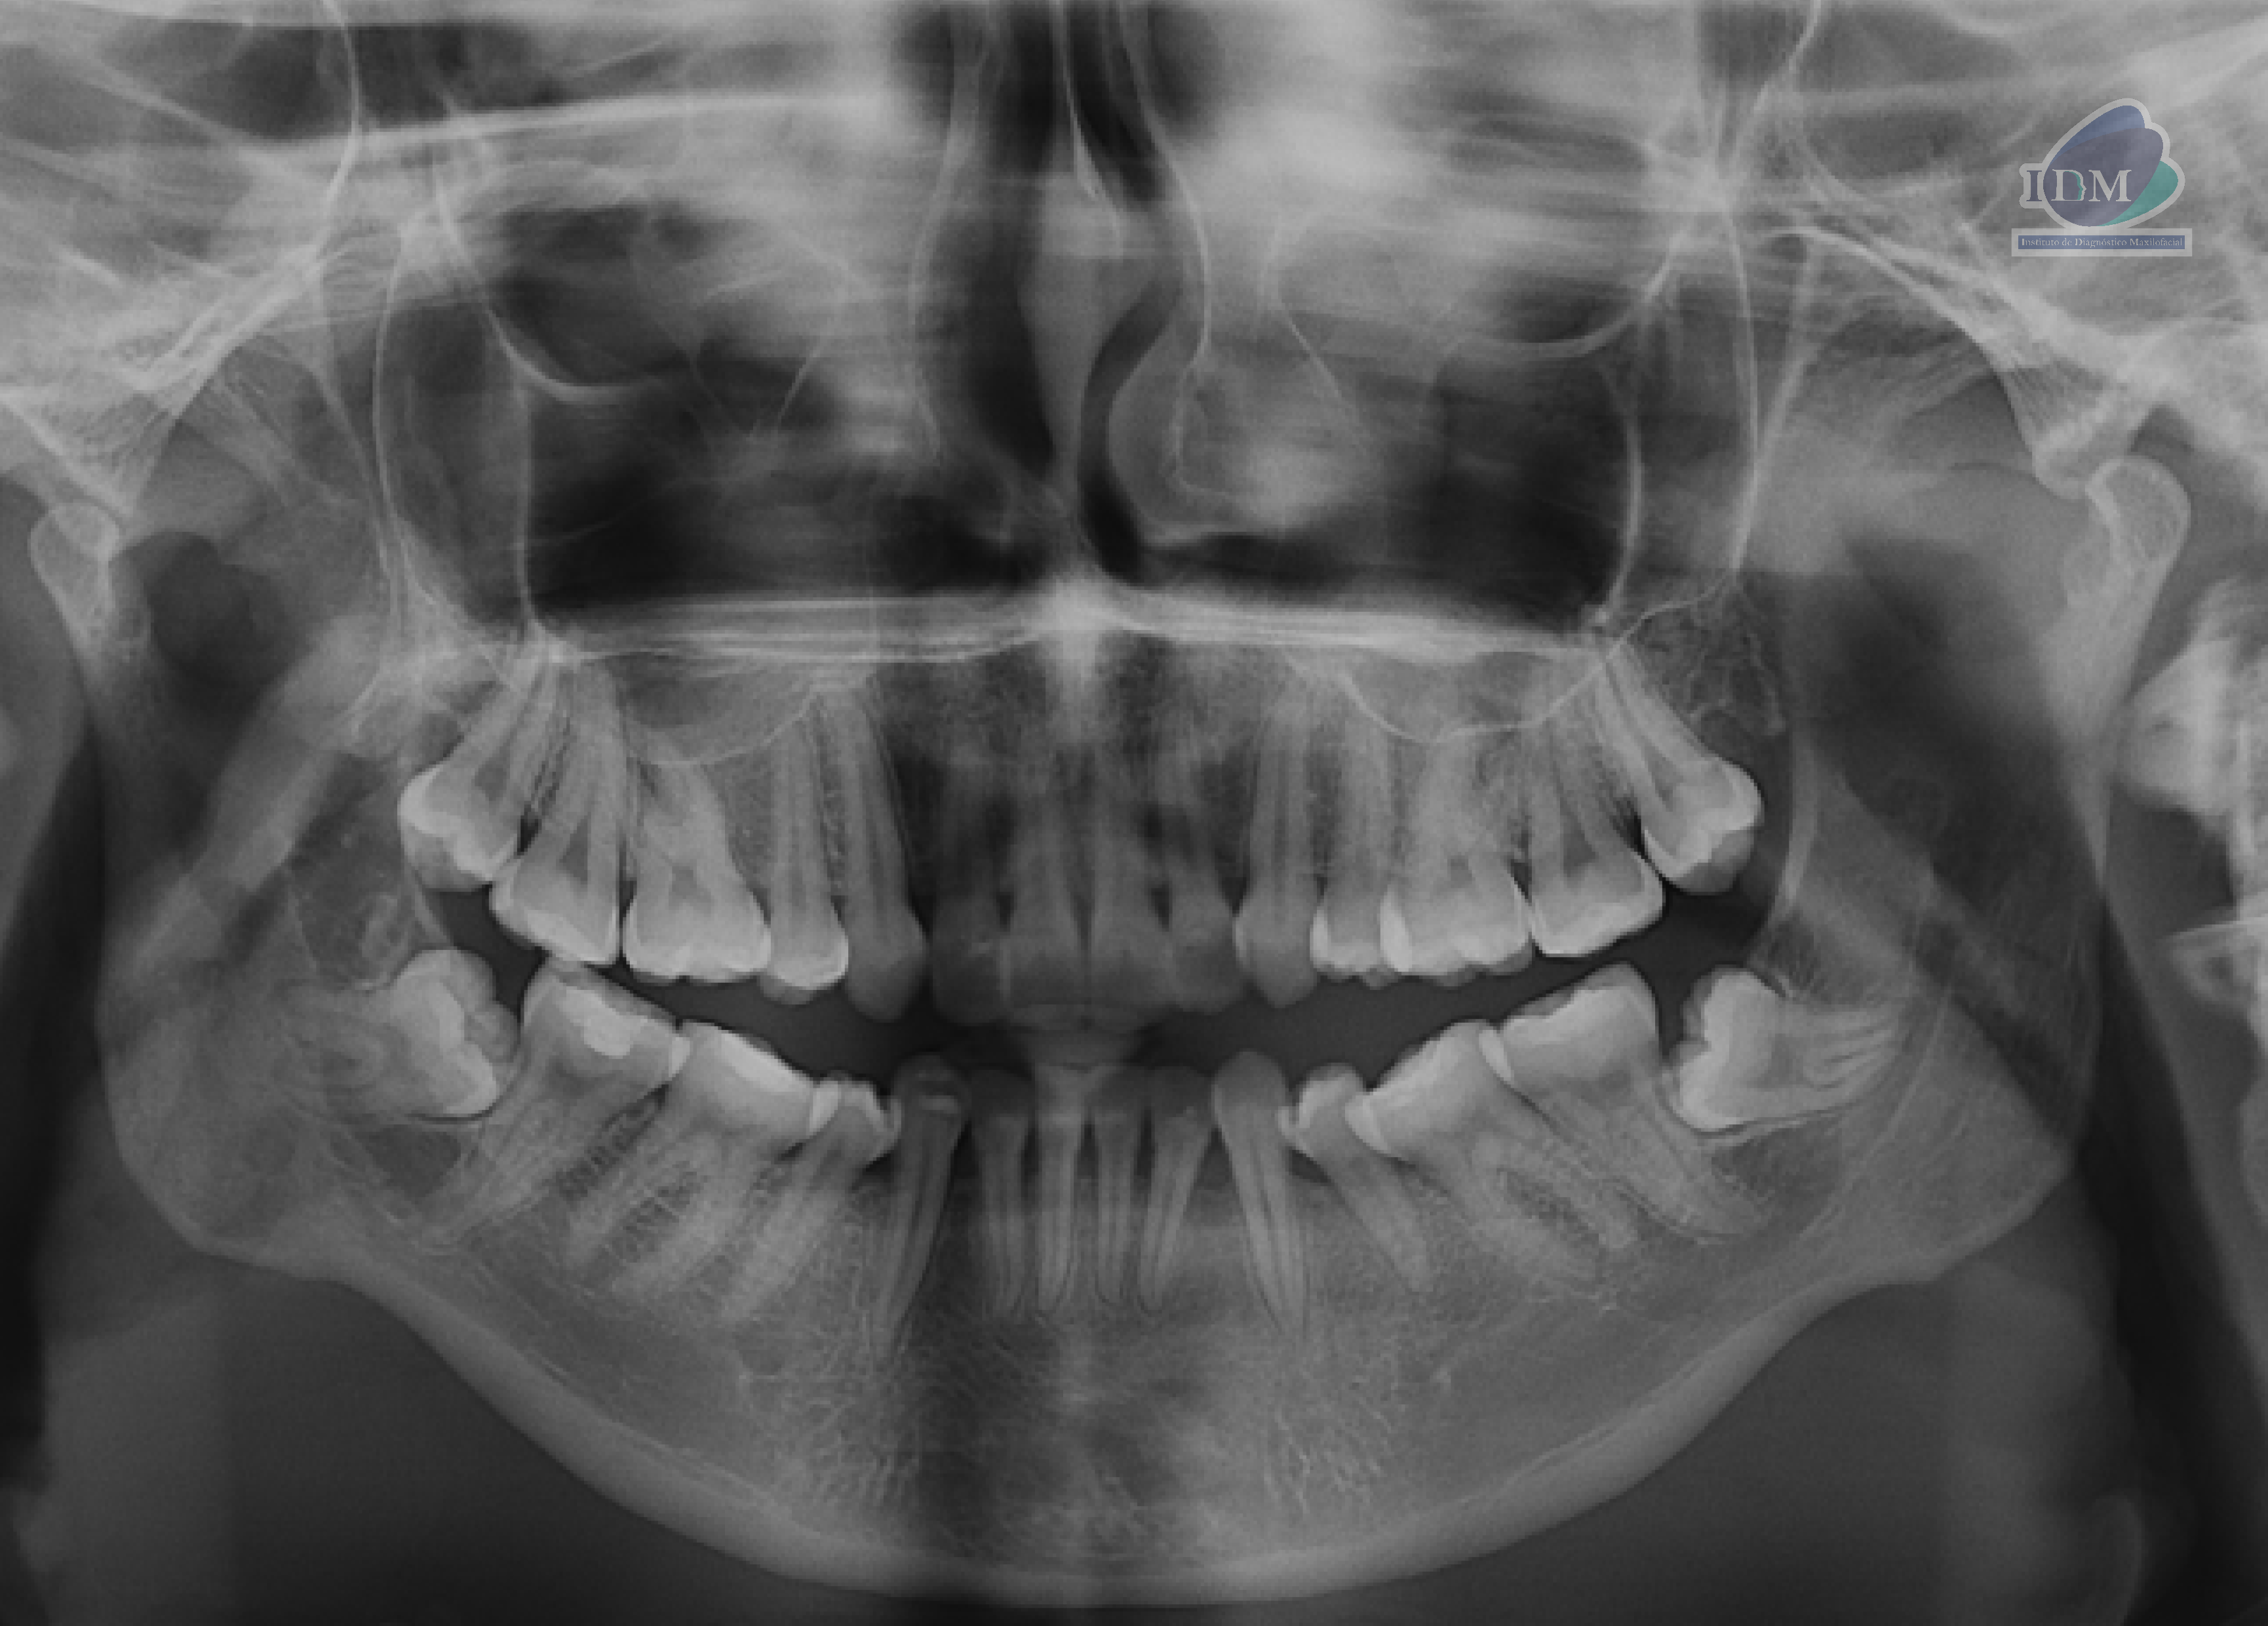

Paciente femenina de 22 años de edad acude al instituto de Diagnóstico maxilofacial – IDM (Sede Surco) para evaluación imagenológica de terceras molares.

En la radiografía panorámica (Figura 1), se observa piezas 38 y 48 mesioanguladas e impactadas contra la superficie radicular distal de las piezas 37 y 47 respectivamente.

Radiografia Panorámica